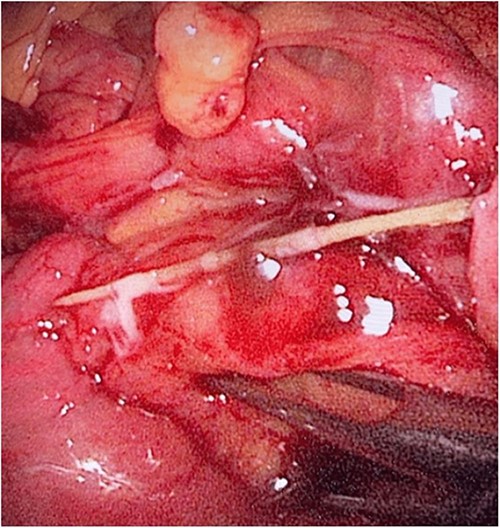

During her hospital stay, the patient showed no improvement regarding abdominal pain, nausea, or abdominal exam. Therefore, she was offered a laparoscopic exploration to verify the diagnosis of a FB to which she agreed. She was taken to the operating room, and the exploration showed an inflammatory process in the LLQ (Fig. 3) with the sigmoid colon attached to the area of the inflammatory reaction. A FB was found in the mesentery of two loops of the ileum 100 cm from the ileocecal junction (Figs 4 and 5). Removal of the FB safely and milking of the small bowel showed no leakage of bowel contents (Fig. 6). And, exploring the rest of the abdomen showed no other pathology and normal ovaries (Figs 7 and 8); the procedure was uneventful. The FB was identified as a toothpick, 3 cm in length (Fig. 9).

The laparoscopic exploration showed a FB in the mesentery of two loops of the ileum 100 cm from the ileocecal junction—upon partial exposure of the site of the toothpick.

The laparoscopic exploration showed a FB in the mesentery of two loops of the ileum 100 cm from the ileocecal junction—after full exposure of the site of the toothpick.